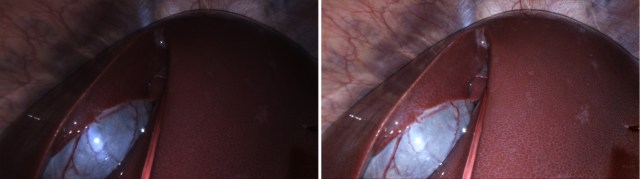

Real-time image/video enhancement for liver endoscopy

This is research in progress. Some related papers can be seen: